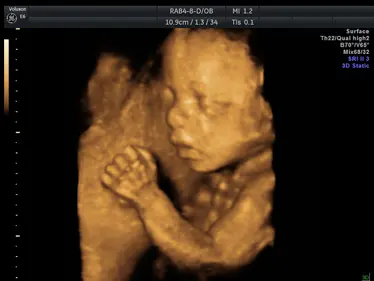

Gallery: 4D Scan Images & Videos

All of the baby scans we perform here at First Encounters are carried out using top-quality ultrasound equipment. For 3D/4D scans, we use the GE Voluson E6, featuring genuine HDLive technology. GE Healthcare are the world’s leading providers of pregnancy scanning equipment, and HD Live scans give an unparalleled level of detail and clarity.

Scroll down to view some examples of the 4D scan images and videos our sonographers are able to capture.

4D Scan Images

During your 3D/4D scan, we’ll capture multiple photographs of your unborn baby, giving you and your family a set of stunning keepsakes that you’ll treasure forever. All of your scan images will be available to download from photocloud™, plus we can provide glossy souvenir photos for you to take home.